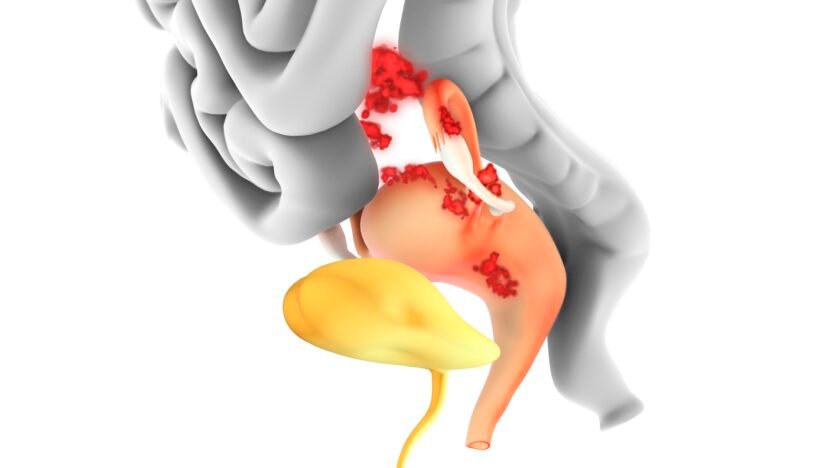

Endometriosis is a painful, debilitating condition affecting 10% of women worldwide. It occurs when tissue similar to the lining of the uterus (known as lesions) grows elsewhere in the body — usually within the pelvis.

Treating endometriosis can be difficult. Usually, treatment involves either preventing the growth of these lesions in the first place or removing lesions surgically. But even when lesions have been surgically removed, symptoms often don’t go away.

Recognizing it as a whole-body, immune-driven disease could help explain why symptoms range far beyond pelvic pain. It would also explain why treatment is so challenging and often does little to reduce symptoms.